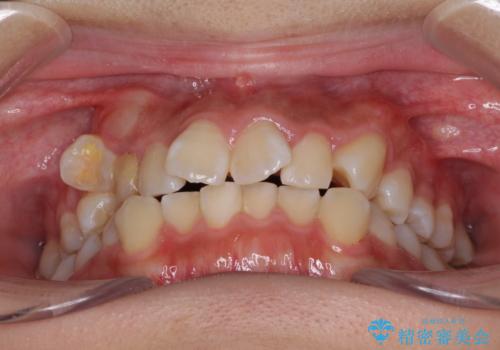

- 前歯のでこぼこと乳歯が残るほどの八重歯を気にして来院された患者様です。

非抜歯にてワイヤー矯正にて治療することとしました。(ただし、親知らずと乳歯は抜歯)

犬歯は歯根が太く長いため、移動には時間を要します。しかし、犬歯は機能面から考えて残すことを選択したいため、長期間をかけて治療を行うこととしました。